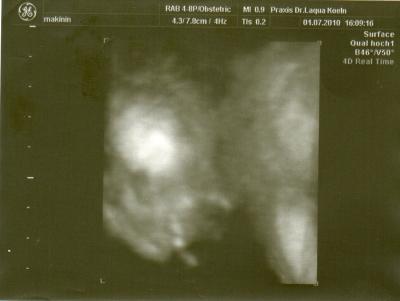

Huhu Ich komme gerade vom FA und mit meiner süßen ist alles supi. Sie ist schon 21 cm groß und hat einen KU von 14 cm Das einzigste, mausi ist so aktiv, dass wir kein ordentliches Foto bekommen, sie dreht sich immer weg hihi kommt wohl nach der Mami LG jenny mit ihrem Babygirl :)

super das alles gut ist...nur auf dem bild kann ich nix erkennen.:-)